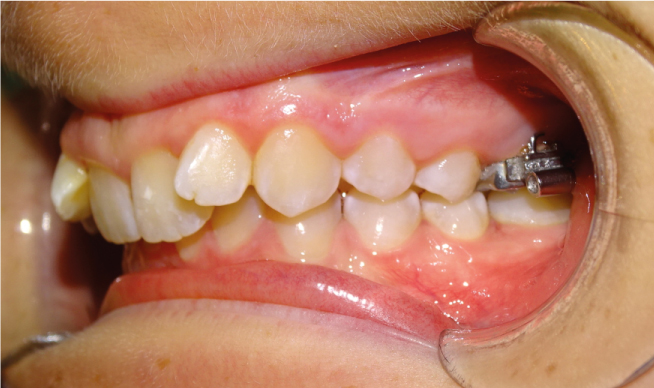

La classe II, c’est quand la mâchoire du bas est en arrière de la mâchoire du haut, donnant l’effet de “dents en avant” pour la mâchoire du haut. Si c’est normal à la naissance, Ceci paraitrait normal à la naissance et tend à se corriger avec l’allaitement maternel et la recherche de contacts entre les incisives du haut et du bas. Au plus on intervient tôt, au plus la mâchoire du bas va rattraper la mâchoire du haut ; au plus on attend, au plus on reculera le haut sur le bas avec des conséquences sur l’esthétique du profil et la capacité ventilatoire nasale.

Dans le cas d’une Classe II :

• La lèvre du bas s’interpose entre les 2 mâchoires

• Le sourire est étroit, tendance à l’écrasement du bas du visage

• Apparition de cernes en relation avec le manque de croissance de la mâchoire du haut

• Difficultés à respirer par le nez et oxygéner le haut du visage